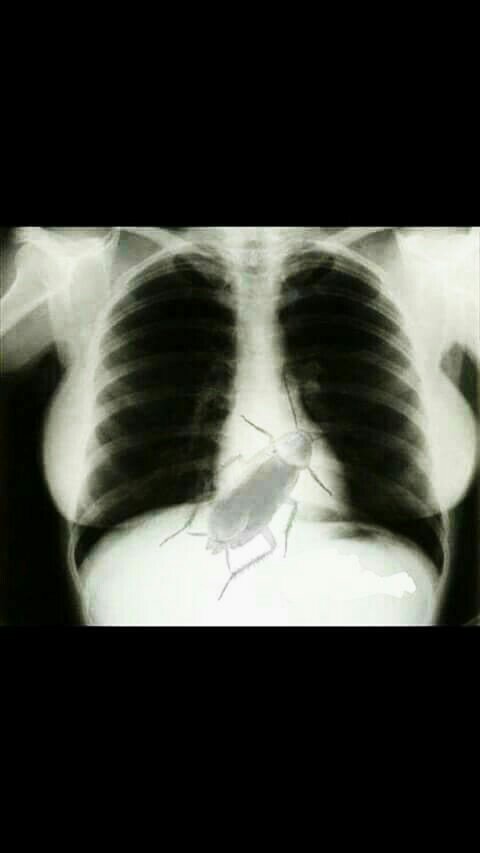

Mfano View attachment 506338

Hiyo ni picha ya x ray ya mtu ambae hajaenda haja kubwa kwa mda mrefu na hivyo vilivyo zungushiwa ni kinyesi! So nitatizo hilo mpeleke Hospital Bro

Mkuu hiyo Ni editing ni kitu ambacho hakiwezekani!....Hapo walitaka kuonesha Maandalizi Mabovu ya Radiographer wakati wa kipimoHii vipi mkuuuu[emoji174][emoji174][emoji174]